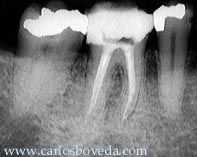

Primer

Molar Inferior Derecho

El

paciente, de 29 años de edad, nos es es

referido para tratamiento endodóntico del

primer molar inferior derecho.

Las

imágenes radiográficas

finales permiten evaluar el tratamiento

realizado.